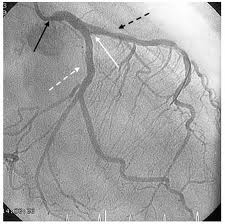

El corazón recibe sangre por vía de las 3 arterias coronarias.

La arteria coronaria principal izquierda, se bifurca en: 1) la arteria descendiente anterior y 2)la arteria circunfleja. Estas aún se dividen en otras ramas más pequeñas. La tercera arteria coronaria es: 3). la arteria coronaria derecha, que también se bifurca en otras ramas más pequeñas. Todas estas arterias y sus ramas son las responsables de suministrarle sangre al músculo del corazón.

y arteria circunfleja